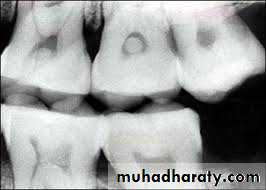

• 4) Periapical granuloma

Periapical granuloma is one of the most common sequele of pulpitis. It is usually described as a mass of chronically inflamed granulation tissue found at the apex of nonvital tooth.Etiology

Radiographic Features

• Mostly discovered on routine radiographic examination

• The earliest change in the periodontal ligament is found to be thickening of ligament at the root apex

• Lesion may be well circumscribed or poorly defined

• Size may vary from small lesion to large radiolucency exceeding more than 2 cm in diameter.